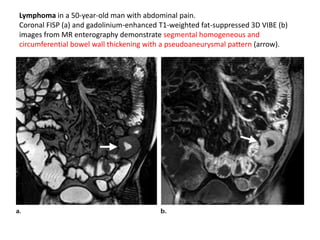

either continuous with or

located adjacent to the GI